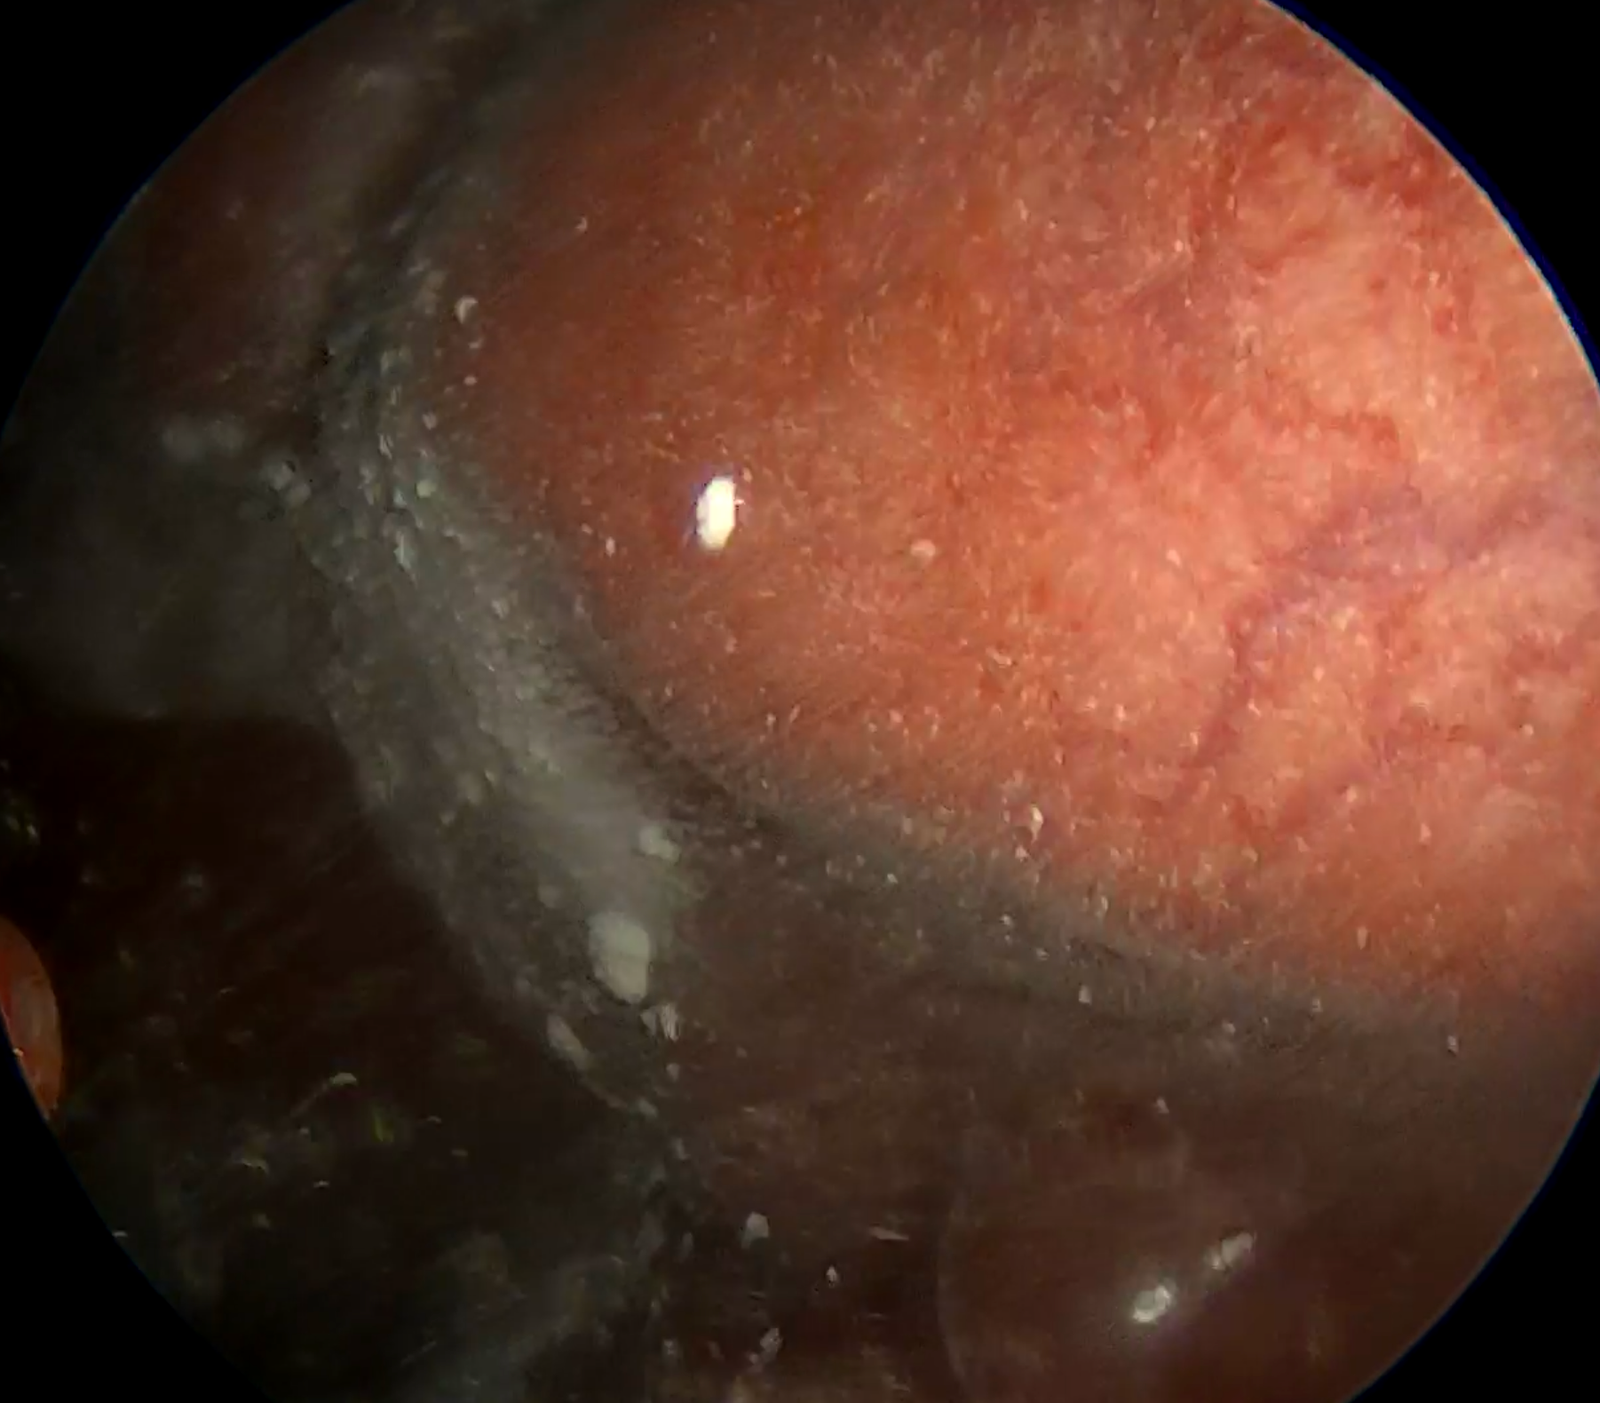

View of the pleural cavity upon thoracoscopic entry: Massive serosanguinous fluid filled the entire pleural cavity. A solitary pleural metastasis is observed.

Figure 2. View of the pleural cavity upon thoracoscopic entry: Massive serosanguinous fluid filled the entire pleural cavity. A solitary pleural metastasis is observed.

Under general anesthesia with single-lung ventilation, the patient was positioned in the left lateral decubitus position. Following antiseptic preparation and sterile draping, a 1-cm incision was made in the right mid-axillary line. A 5 mm trocar was introduced into the pleural cavity, and a medical thoracoscope was advanced under direct visualization. A large hemorrhagic effusion was encountered (Figure 2.). A secondary incision was created inferiorly for the insertion of a second trocar, which permitted aspiration of the remaining pleural fluid. In total, approximately 1.2 liters were evacuated.